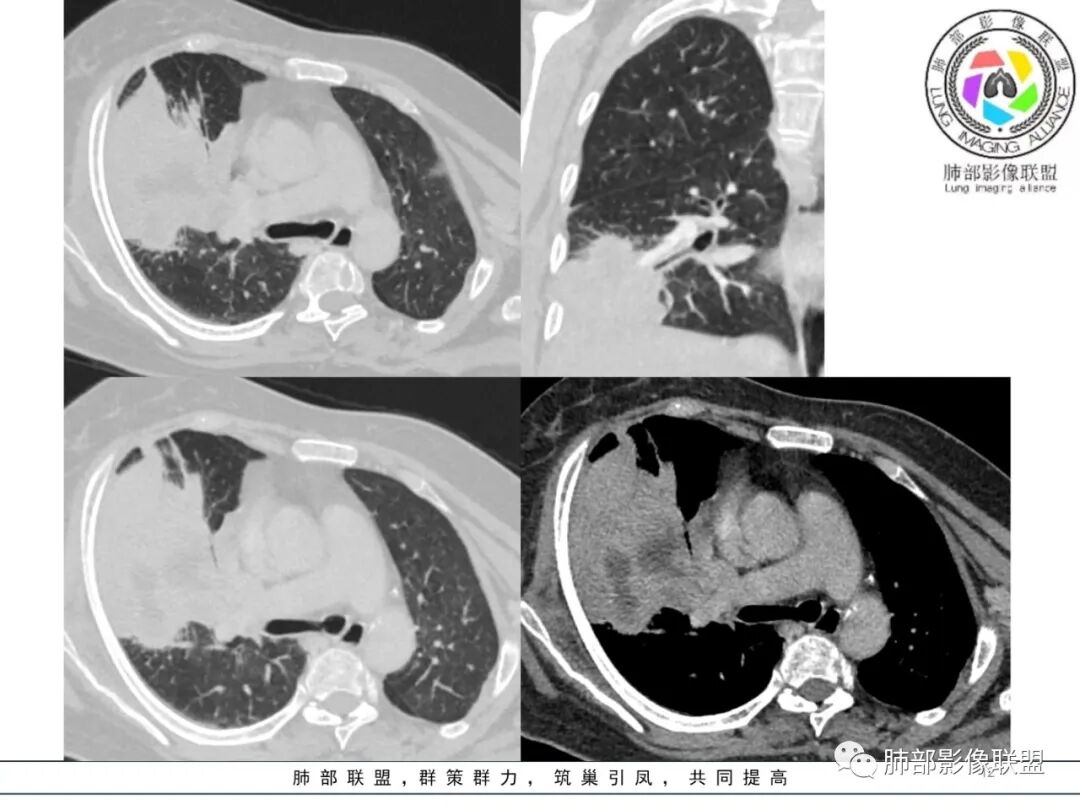

三、补充重建图像

四、晨读结果

五、南边精彩复盘

南边:跨叶、楔形/边缘平直、支气管壁无破坏/连续/局部无膨大、实变区肺动脉走形自然、实性部分均匀、延迟强化、坏死腔内壁光滑/内壁强化环/近端与支气管相通,这些点均支持炎性。所以综合分析:符合炎性。